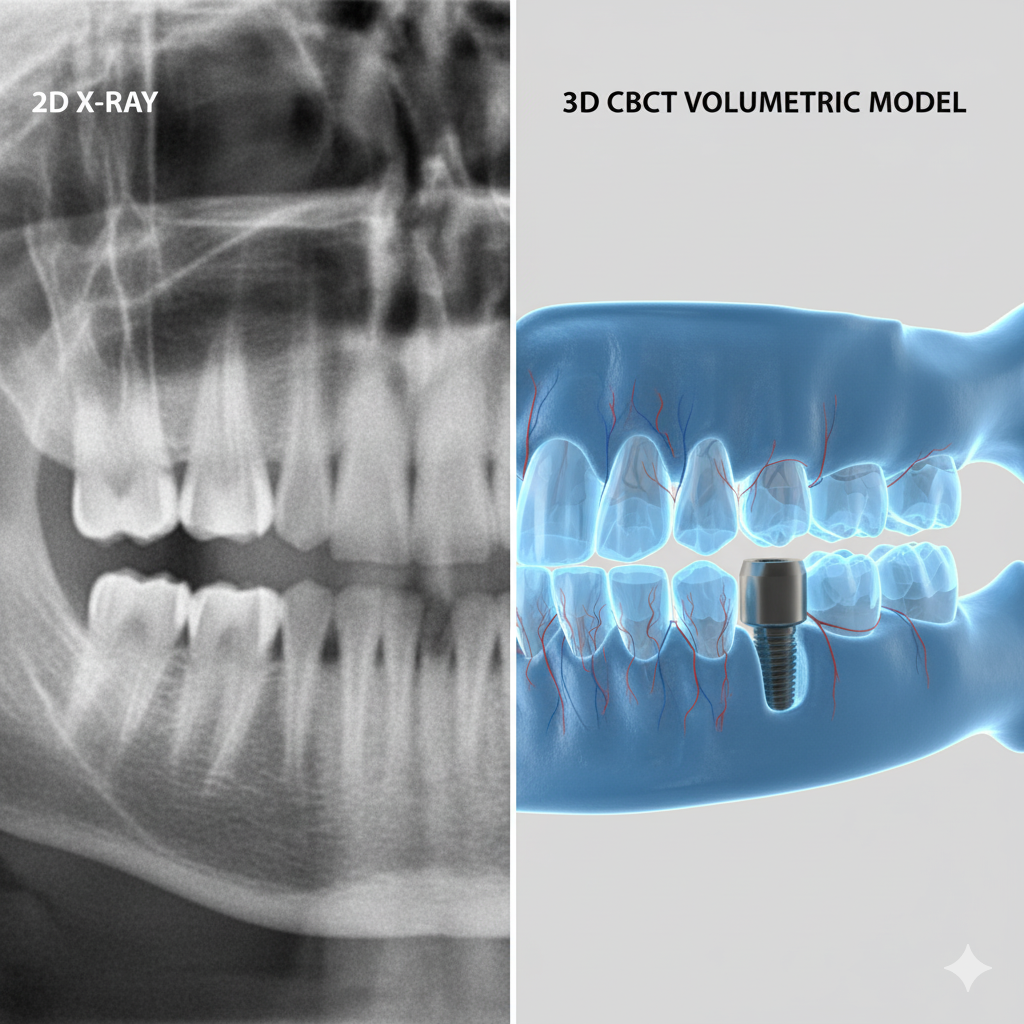

Digitales 3D-Röntgen (DVT)

Präzise 3D-Diagnostik für Implantate und komplexe Behandlungen

Unser modernes DVT-Gerät ermöglicht dreidimensionale Aufnahmen des Kiefers mit

minimaler Strahlenbelastung. Die präzisen 3D-Bilder sind Grundlage für

implantologische Behandlungen, Wurzelkanaltherapien und die Planung komplexer

zahnärztlicher Eingriffe.

Geringste Strahlenbelastung im Vergleich zu herkömmlichen Röntgengeräten

Hochpräzise 3D-Bilder für exakte Behandlungsplanung

Schnelle Aufnahme in nur wenigen Sekunden

Komfortable und angstfreie Untersuchung für Patienten